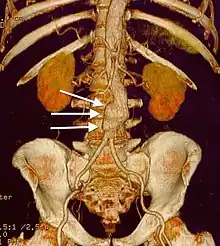

three white arrows pointing to an enlargement of the abdominal aorta

CT reconstruction image of an abdominal aortic aneurysm (white arrows)